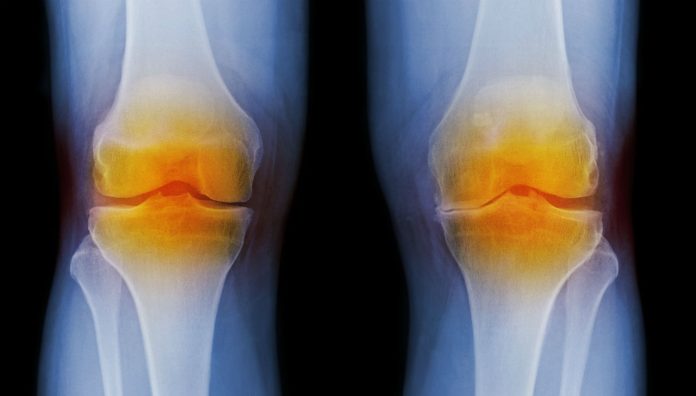

Osteoarthritis (OA) is a chronic disease that usually affects the hands, knees and hips.1,2 The main symptoms are joint pain and stiffness that usually develop slowly over time.3 It can get to a point where everyday tasks become difficult.3

Traditionally, OA was thought to be a non-inflammatory disease resulting from ‘wear and tear’ that leads to loss of cartilage.2,4 However, research into the condition has revealed that inflammation plays a role in OA pain.4,5 In a holistic management approach for OA sufferers, pain management is an important aspect.1